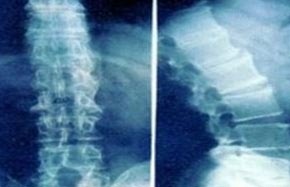

济南强直性脊柱炎研究所科室诊疗

打造强直性脊柱炎规范化临床知识库特色技术